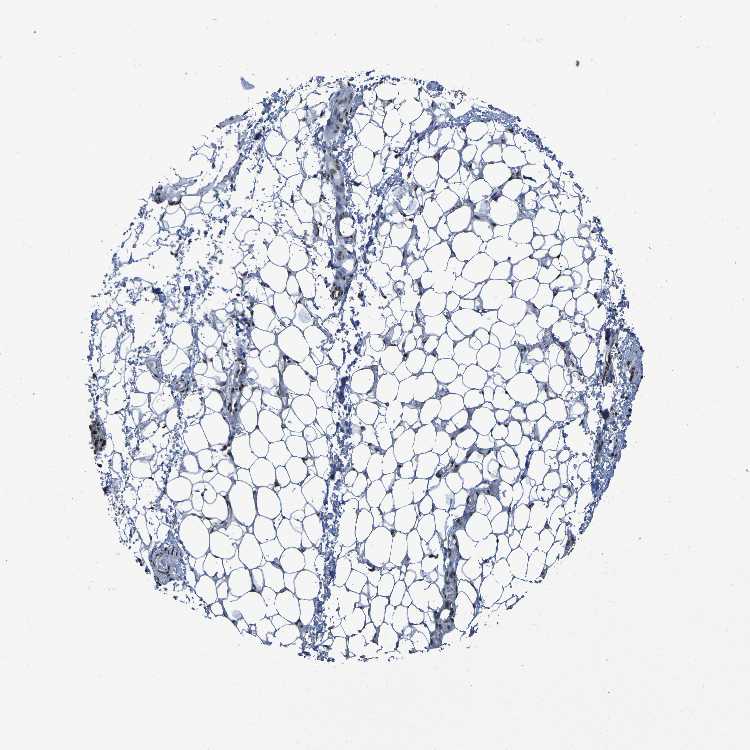

SOFT TISSUE 1 - Antibody stainingi

Antibody staining in the annotated cell types in the current human tissue is reported as not detected, low, medium, or high, based on conventional immunohistochemistry profiling in selected tissues. This score is based on the combination of the staining intensity and fraction of stained cells.

Each image is clickable and will lead to virtual microscopy that enables deeper exploration of all samples and also displays staining intensity scores, fraction scores and subcellular localization as well as patient and tissue information for each sample.

Antibody HPA026092Antibody CAB011687

Chondrocytes Medium-

Fibroblasts Not detectedHigh

Peripheral nerve Not detectedHigh